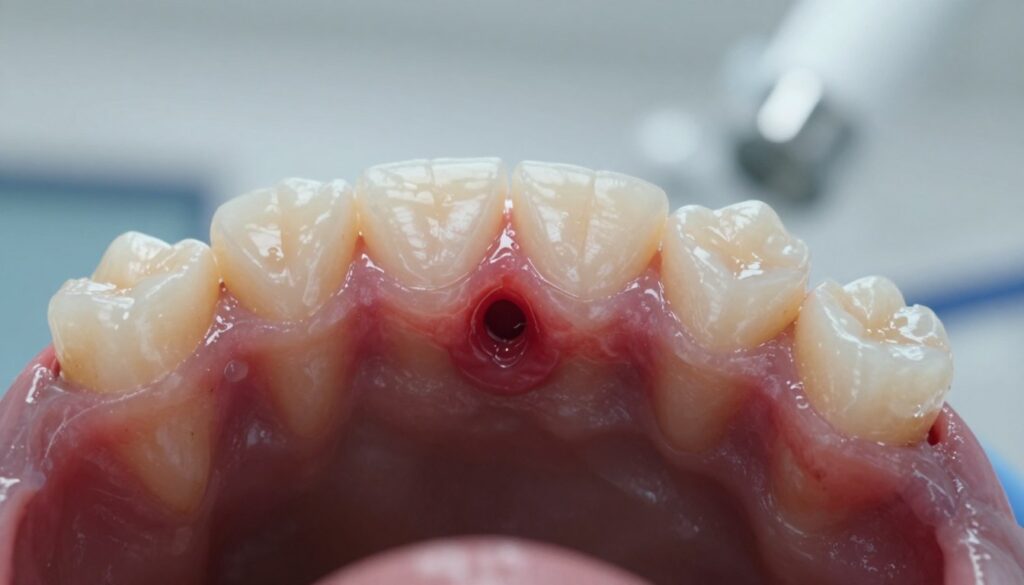

Przetoka zębowa to kanał drenażowy, którym organizm odprowadza ropę z przewlekłego ogniska zapalnego przy korzeniu zęba. W praktyce widzimy małe uwypuklenie na dziąśle, czasem z białawym czubkiem lub widocznym ujściem.

- Jak wygląda: mały guzek na dziąśle z ewentualnym sączeniem ropy.

- Skąd wydzielina: ropna lub krwisto-ropna, wynik zakażenia tkanek.

- Samokontrola: sprawdź w lustrze ujście w jamie ustnej; pojawienie się wydzieliny wymaga konsultacji.